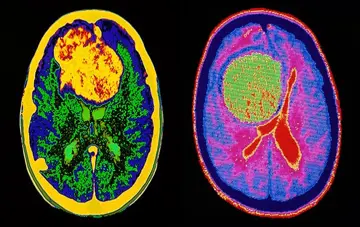

ابداع روش نوین درمانی و افزایش طول عمر و کیفیت زندگی مبتلایان به تومور مغزی بدخیم

رییس دانشگاه علوم پزشکی شهید بهشتی خبر از افزایش طول عمر و کیفیت زندگی بیماران مبتلا به تومور بدخیم مغزی با ابداع روشی نوین برای نخستین بار در جهان توسط متخصصان جراح مغز و اعصاب و ستون فقرات این دانشگاه داد.

دکتر فرهادعصارزادگان ، دانشیار دانشگاه علوم پزشکی شهید بهشتی از تولید جدیدترین داروی ضد لخته جهت درمان بیماران دچار سکته مغزی خبر داد.